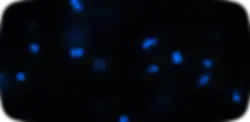

Cytotoxicity

Nuclei Loss and Morphology

Hoechst (Nuclei)